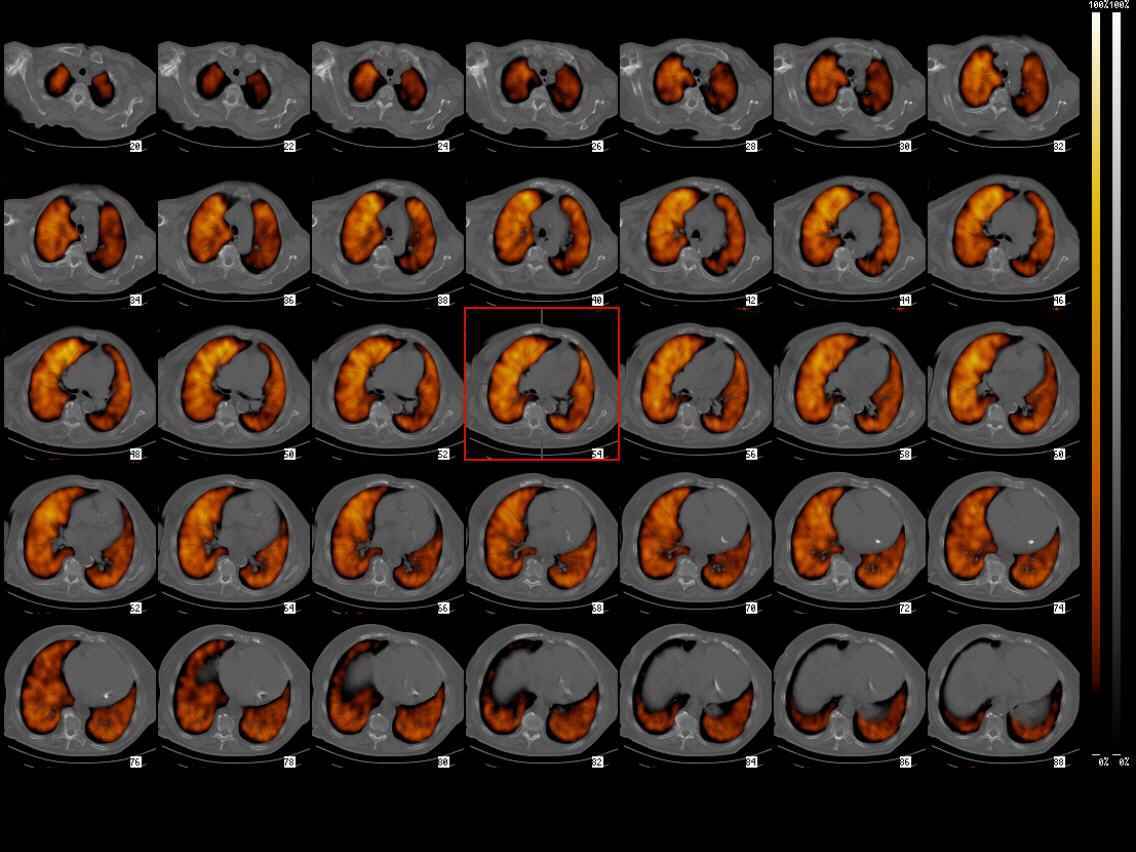

Mikrospopisch kleine, radioaktiv markierte Eiweißpartikel werden in die Vene gespritzt und zeigen in den Szintigrammen an, ob und an welcher Stelle eine Lungenembolie stattgefunden hat. Die Aufnahmen erfolgen von verschiedenen Seiten und im Schnittbildverfahren (Single Photonen Emissions Computertomographie - SPECT)

Da Perfusionsdefekte der Lunge nicht nur wegen einer Emolie, sondern auch bei anderen Lungenerkrankungen wie zum Beispiel Pneumonie oder Tumoren vorkommen können, ist ein Vergleich mit einer Röntgenaufnahme sinnvoll. Hierfür wurden im Beispiel eine Röntgen - Computertomographie und eine SPECT der Lunge übereinander gelegt (SPECT-CT)